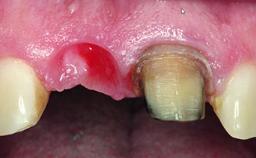

Replacement of a Failing Upper Left Central Incisor: Immediate Placement of an RC Bone Level Implant and Provisionalization

A healthy 23-year-old female patient was referred for a consultation on replacing tooth 21 with an implant-supported restoration. The patient had recently moved to the area and reported a history of endodontic and periodontal treatment for tooth 21. The tooth had been deemed non-restorable by her previous periodontist but since she was going to be moving, he recommended consulting to a dentist in her new city to continue her treatment. A review of her medical history yielded no significant findings and no known drug allergies. The analysis of her smile revealed a medium to high symmetrical smile line and a slightly discolored tooth 21.

Placement Protocol Immediate implant placement

Socket Integrity Damage to one or more bone walls